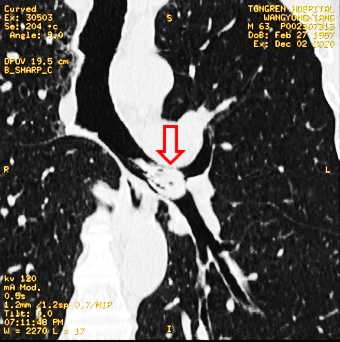

章医生:“你的胸部ct我看了下,是虾呛到气管里了,要马上在气管镜下取出来。”

(ct结果显示王先生的左肺有一只虾)

片刻,严主任已赶到并准备就位。只见镜头进入左总支气管,一只河虾的额刺赫然在目,完全阻塞了气管腔。所幸,额刺并没有扎入气管道引起大出血,不然后果不堪设想。